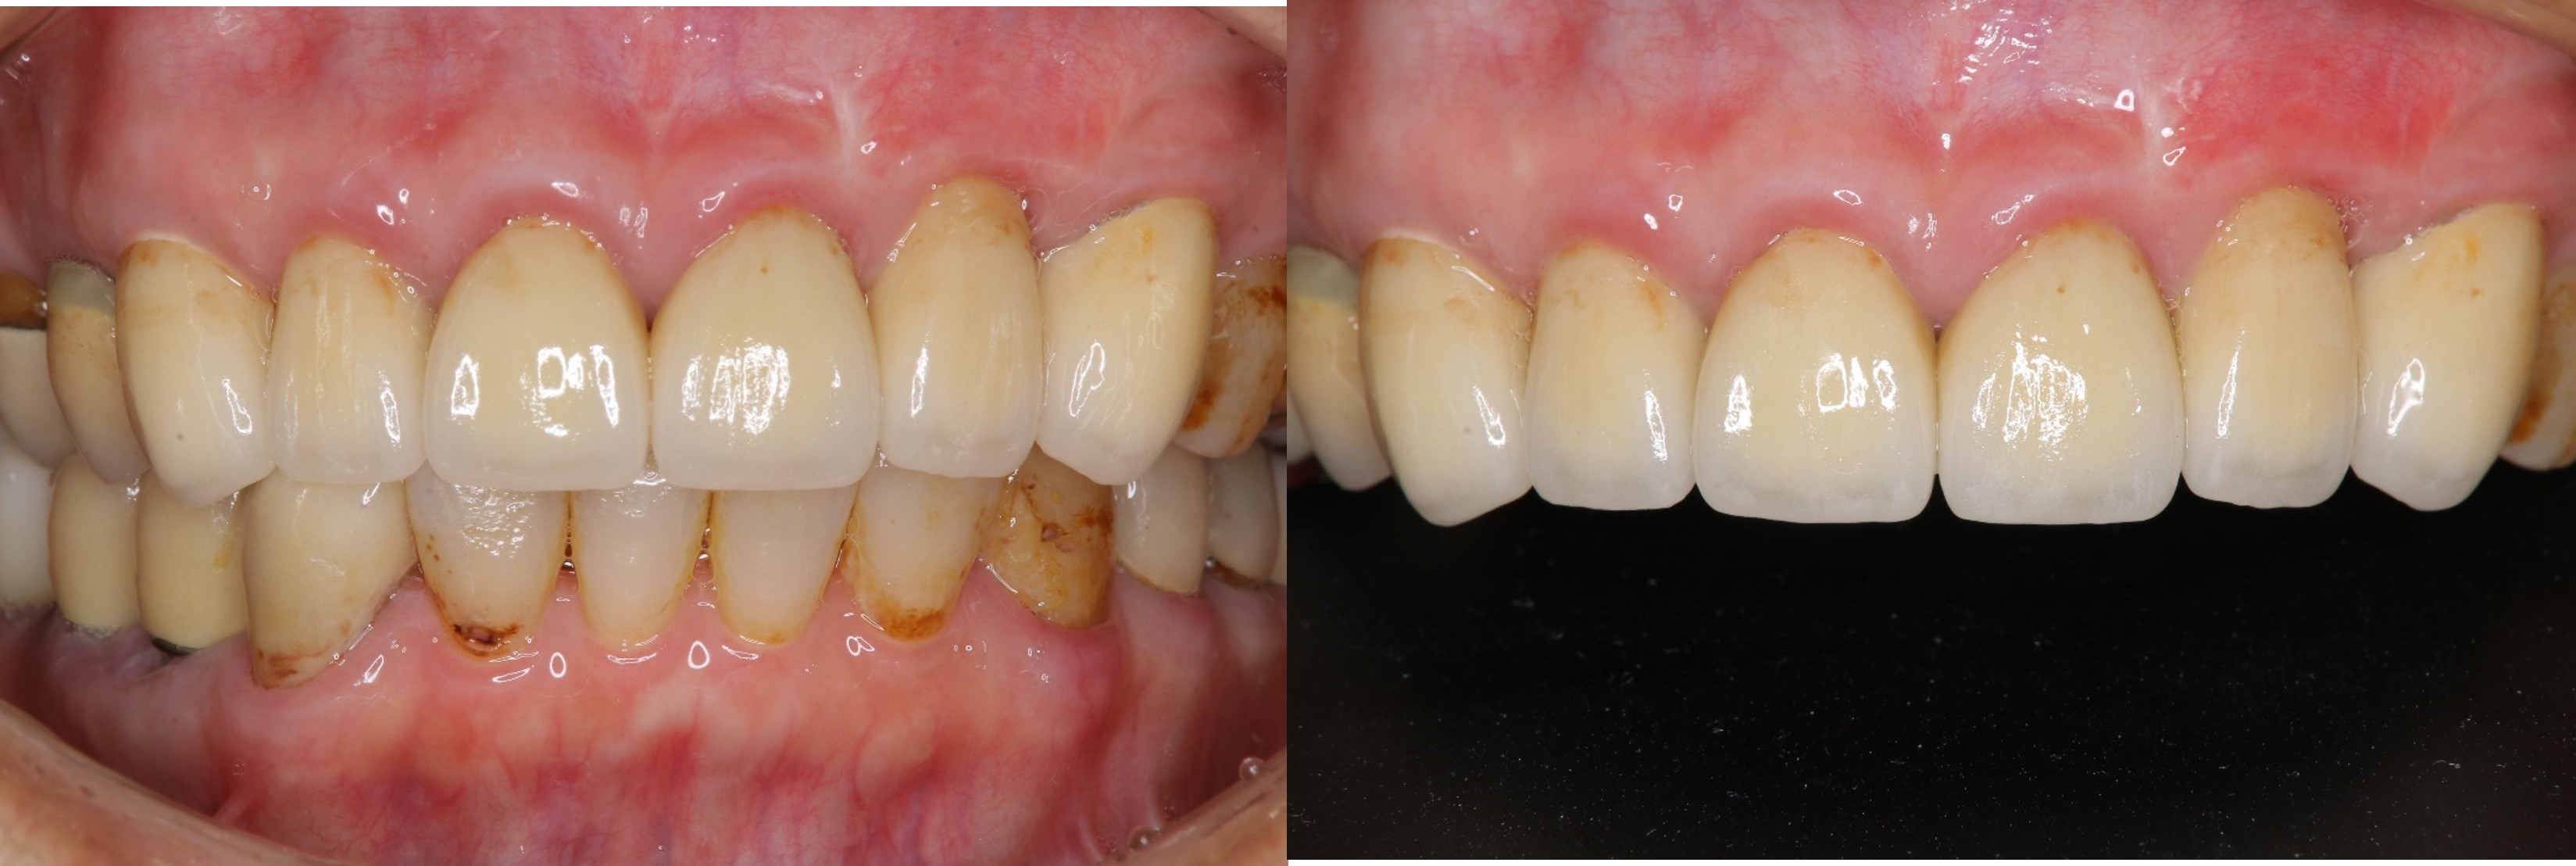

術前、術後比較